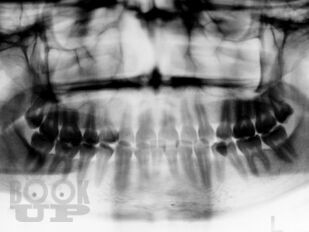

В учебном пособии на современном исследовательском уровне обобщены и подробно изложенылечение и профилактика заболеваний пародонта. Схемы этиопатогенетического лечения заболеваний пародонта постоянно совершенствуются и с успехом используются на протяжении многих лет на кафедре терапевтической стоматологии и в поликлиниках города. Авторы надеются, что издание поможет врачам-стоматологам, а также врачам других специальностей в назначении комплексного, индивидуализированного, этиопатогенетического лечения заболеваний пародонта.